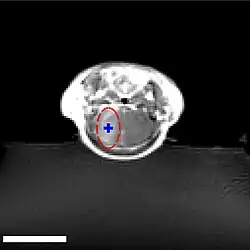

Der Fokus des Ultraschalls kann auf beliebige Areale im Gehirn gerichtet werden. Dadurch kann die Blut-Hirn-Schranke selektiv, auf bestimmte Hirnareale begrenzt, geöffnet werden. So können applizierte Wirkstoffe gezielt in diese Areale diffundieren.[140] Die behandelten Areale lassen sich durch eine simultan laufende Magnetresonanztomographie (MRT) genau verfolgen. Dabei dringt das für die MRT verwendete Kontrastmittel, beispielsweise Gadopentetat-Dimeglumin, nur durch die geöffneten Areale der Blut-Hirn-Schranke in das Gehirn ein. Diese Bereiche werden dadurch im MRT deutlich sichtbar hervorgehoben. Das hochpolare Gadopentetat-Dimeglumin ist nicht in der Lage die ungeöffneten Bereiche der Blut-Hirn-Schranke zu passieren.

Im Tiermodell Maus werden bei der Anwendung von fokussiertem Ultraschall mit Mikrobläschen Frequenzen im Bereich von 0,5 und 2 MHz[141] mit kurzen Pulslängen im Millisekundenbereich und Wiederholfrequenzen im Bereich von 1 Hz, über einen Zeitraum von weniger als einer Minute angewendet.[142] Der optimale Frequenzbereich liegt unterhalb von 1 MHz.[143] Die akustische Leistung beträgt weniger als ein Watt. Die verwendeten Mikrobläschen sind meist zugelassene Kontrastmittel aus der kontrastmittelverstärkten Sonographie. Sie haben typischerweise einen Durchmesser von 3 bis 4,5 µm, bestehen beispielsweise aus Humanalbumin und sind mit Perfluorpropan oder ähnlichen Schwergasen gefüllt.[144]

Der Mechanismus zur Öffnung der Blut-Hirn-Schranke durch die Anwendung von fokussiertem Ultraschall, zusammen mit Mikrobläschen, ist noch nicht vollständig aufgeklärt. Die Wechselwirkung von Ultraschall und Mikrobläschen spielt dabei eine große Rolle und führt in vivo zu einer Reihe von biologischen Effekten.[145] Eine wesentliche Rolle scheinen dabei Scherkräfte zu spielen, die durch Mikroströmungen erzeugt werden. Diese Mikroströmungen selbst kommen von Oszillationen der Mikrobläschen im Ultraschallfeld.[145] Von den Endothelien selbst ist wiederum bekannt, dass sie auf Scherkräfte dynamisch reagieren können und Scherkräfte eine kritische Größe für die Homöostase sind.[146] Elektronenmikroskopische Aufnahmen von Kapillargefäßen so behandelter Versuchstiere zeigen sowohl einen transzellulären als auch einen parazellulären Transport von entsprechenden Markermolekülen (Meerrettichperoxidase). Bei dem transzellulären Transport handelt es sich im Wesentlichen um Transzytose. Der parazelluläre Transport wird durch einen komplexen Desintegrationsprozess initiiert, bei dem die Tight Junctions ihre Funktion verlieren.[147]

Die so geöffnete Blut-Hirn-Schranke ist durchlässig für niedermolekulare Chemotherapeutika, wie beispielsweise Doxorubicin[148] und Antikörper, wie Trastuzumab.[149][150][151] Auch die prinzipielle Machbarkeit des Transports von Genen in das Gehirn wurde mit dieser Methode im Tiermodell nachgewiesen.[144][152] Das Verfahren zur Öffnung der Blut-Hirn-Schranke mit Ultraschall und gleichzeitig applizierten Mikrobläschen ist noch ein sehr junges Verfahren. Bisher wurde es nur an Versuchstieren erprobt. Bis zu einer möglichen Zulassung des Verfahrens am Menschen vergehen erfahrungsgemäß noch viele Jahre.